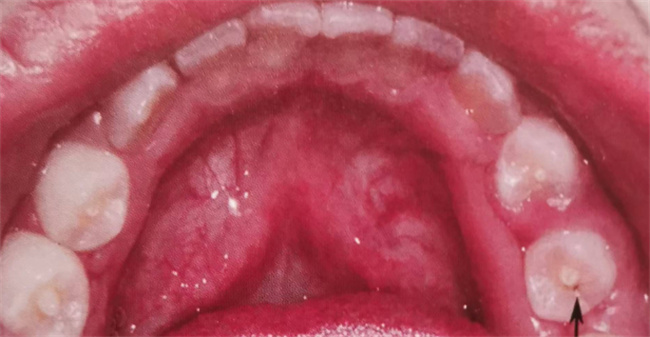

畸形中央尖是一种先天性牙齿发育畸形,主要是由于受遗传因素的影响,牙发育期间,牙乳头组织向成釉器突起,在此基础上形成牙釉质和牙本质,畸形中央尖的突起即为牙齿咬合面的中央窝上的圆锥形突起,高度一般在1-3mm之间,其中有一半的畸形中央尖有牙神经伸入。如果不及时加以防护,就会引起中央尖折断或过度磨损。

一般对于没有症状且较圆钝的中央尖可以定期观察,不予处理。而对于尖而细长的中央尖,则可以通过调整对颌牙,多次少量地调磨该牙尖,从而避免中央尖折断或过度磨损;也可以在伸入的髓角上部形成修复性牙本质层以防止牙神经外露。而如果已经发现畸形中央尖引起牙痛的问题,一般会采用根尖发育成形术或根尖诱导成形术进行治疗。